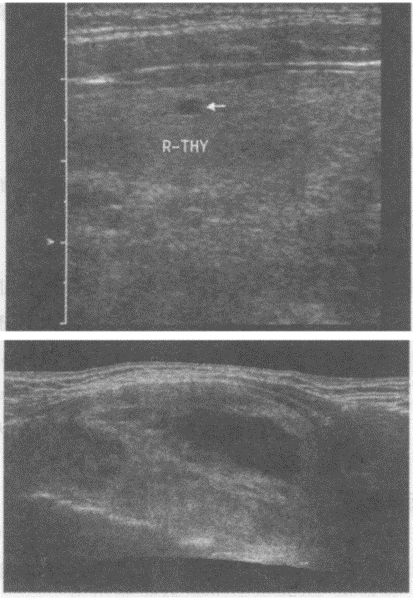

4、单项选择题

患者,女性,甲状腺肿大。探及多个结节状的强回声光团,其内可见暗区。如图所示,最可能的诊断为()。

A.甲状腺功能亢进

B.甲状腺腺瘤

C.甲状腺炎

D.结节性甲状腺肿

E.甲状腺癌

5、单项选择题 结节性甲状腺肿最常见的原因是()。